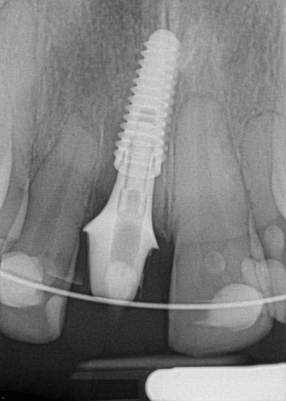

Figure 6 and Figure 7 depict a mature smile with many implant restorations. An analog impression was sent to the laboratory. The impression was scanned by the laboratory, a model was created virtually, and the implant dimensions and position were defined. The 3D surgical guide was fabricated (Figure 8), allowing the patient to receive his therapy swiftly and predictably. Tooth No. 8 was extracted, and the implant was placed and immediately loaded with an acrylic provisional treatment crown (Figure 9). The screw-retained treatment crown was fabricated in-office from a previously completed diagnostic wax-up.

After 4 months of healing and integration of the bone around the implant, the digital workflow was initiated to develop the abutment and treatment plan. Another analog impression was made with an impression post and polyvinyl impression. The laboratory scanned the impression and digitized it to create the emergence profile of the milled titanium abutment and the final restoration (Figure 10 and Figure 11). The patient had a considerably thick soft-tissue profile, allowing a milled titanium abutment. The decision to use a titanium abutment was based on the patient's occlusion and propensity to fracture teeth or restorations. The virtual model was gray because the scanner does not recognize the color of the analog impression. The virtual final abutment and crown were approved and fabrication completed. The final restoration met the patient's esthetic values and his ability to function (Figure 12 and Figure 13).

Fig 7. Radiograph showing the patient’s multiple implant restorations.

Figure 7

Fig 9. Surgery day with immediately loaded implant and treatment crown.

Figure 9

Fig 12. Six months after cementation.

Figure 12

Fig 13. Radiograph 6 months after cementation.

Figure 13